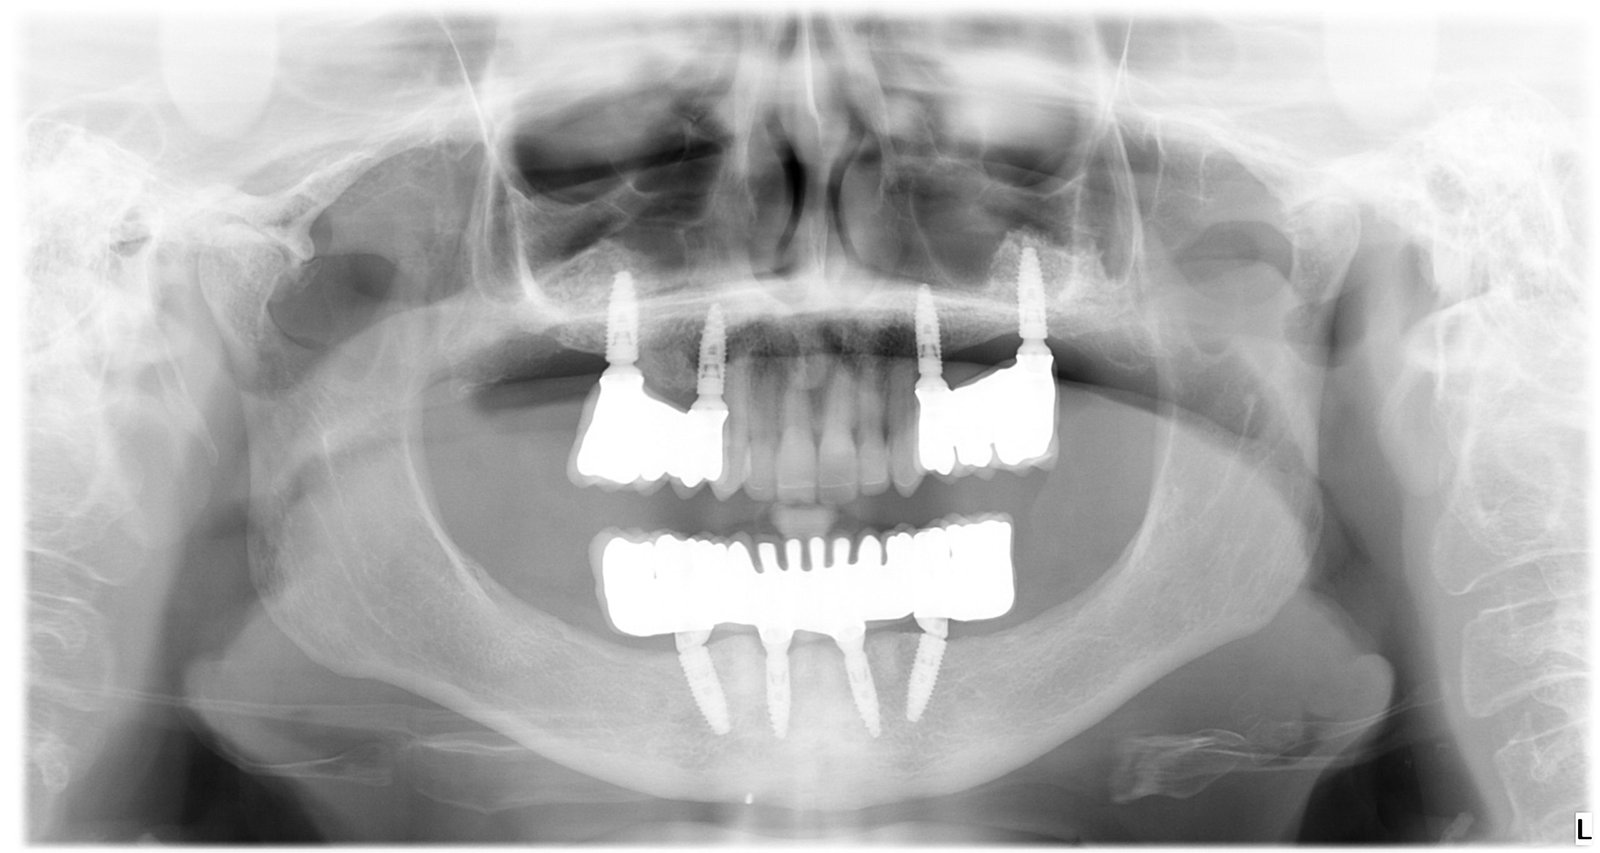

Caso 2 - caso de Estética dental

La paciente acudió preocupada por la estética de su sonrisa y el desgaste de varias piezas dentales. Mediante una rehabilitación estética personalizada mejoramos forma, color y armonía dental, devolviéndole una sonrisa natural, equilibrada y acorde a sus facciones.

El estudio radiológico permitió valorar el estado general de la dentición y planificar la rehabilitación con precisión. Tras el tratamiento, la imagen confirma una estructura dental estable y funcional que garantiza durabilidad y confort.

Esta radiografía muestra la planificación y el resultado de la rehabilitación, evidenciando la correcta integración de las estructuras dentales. Un trabajo orientado a mejorar tanto la función como la estética de forma segura y predecible.